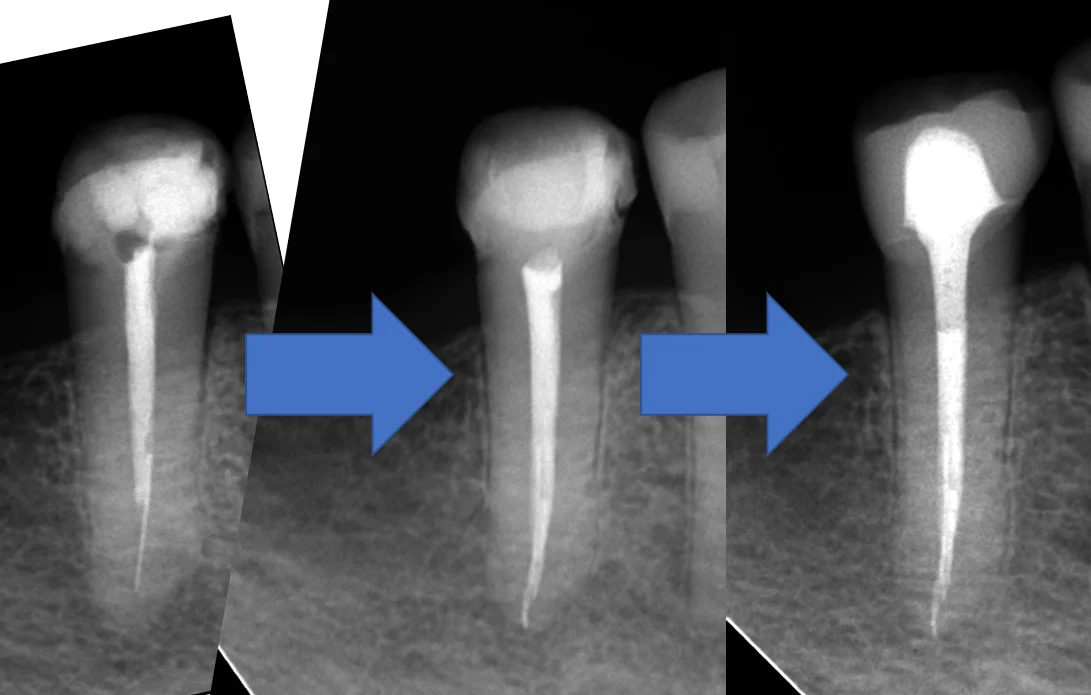

無事に折れたファイルを除去することができ、根の先まで綺麗に到達することが出来ました。

今回はトータルで2ヶ月掛かっていますが、根管充填時点では根の先の骨に明らかな治癒傾向は認められませんでした。

それがこちらです。

根の先には骨がしっかりと出来てくれています。(青い丸の部分)

膿があった影も完全に消失することが出来ましたね。

また入れていたセラミックの適合も非常に良好です。(紫の丸の部分)

段差も一切なく、非常に適合良く入っているのが分かるかと思います。

術前からの比較がこちらです。

分かりやすい様に角度を変えているんですが、若干トリミングに難があるのは許してください。

こうやって比較でみると根の先の膿があった所が消失しているのが分かりやすいかと思います。